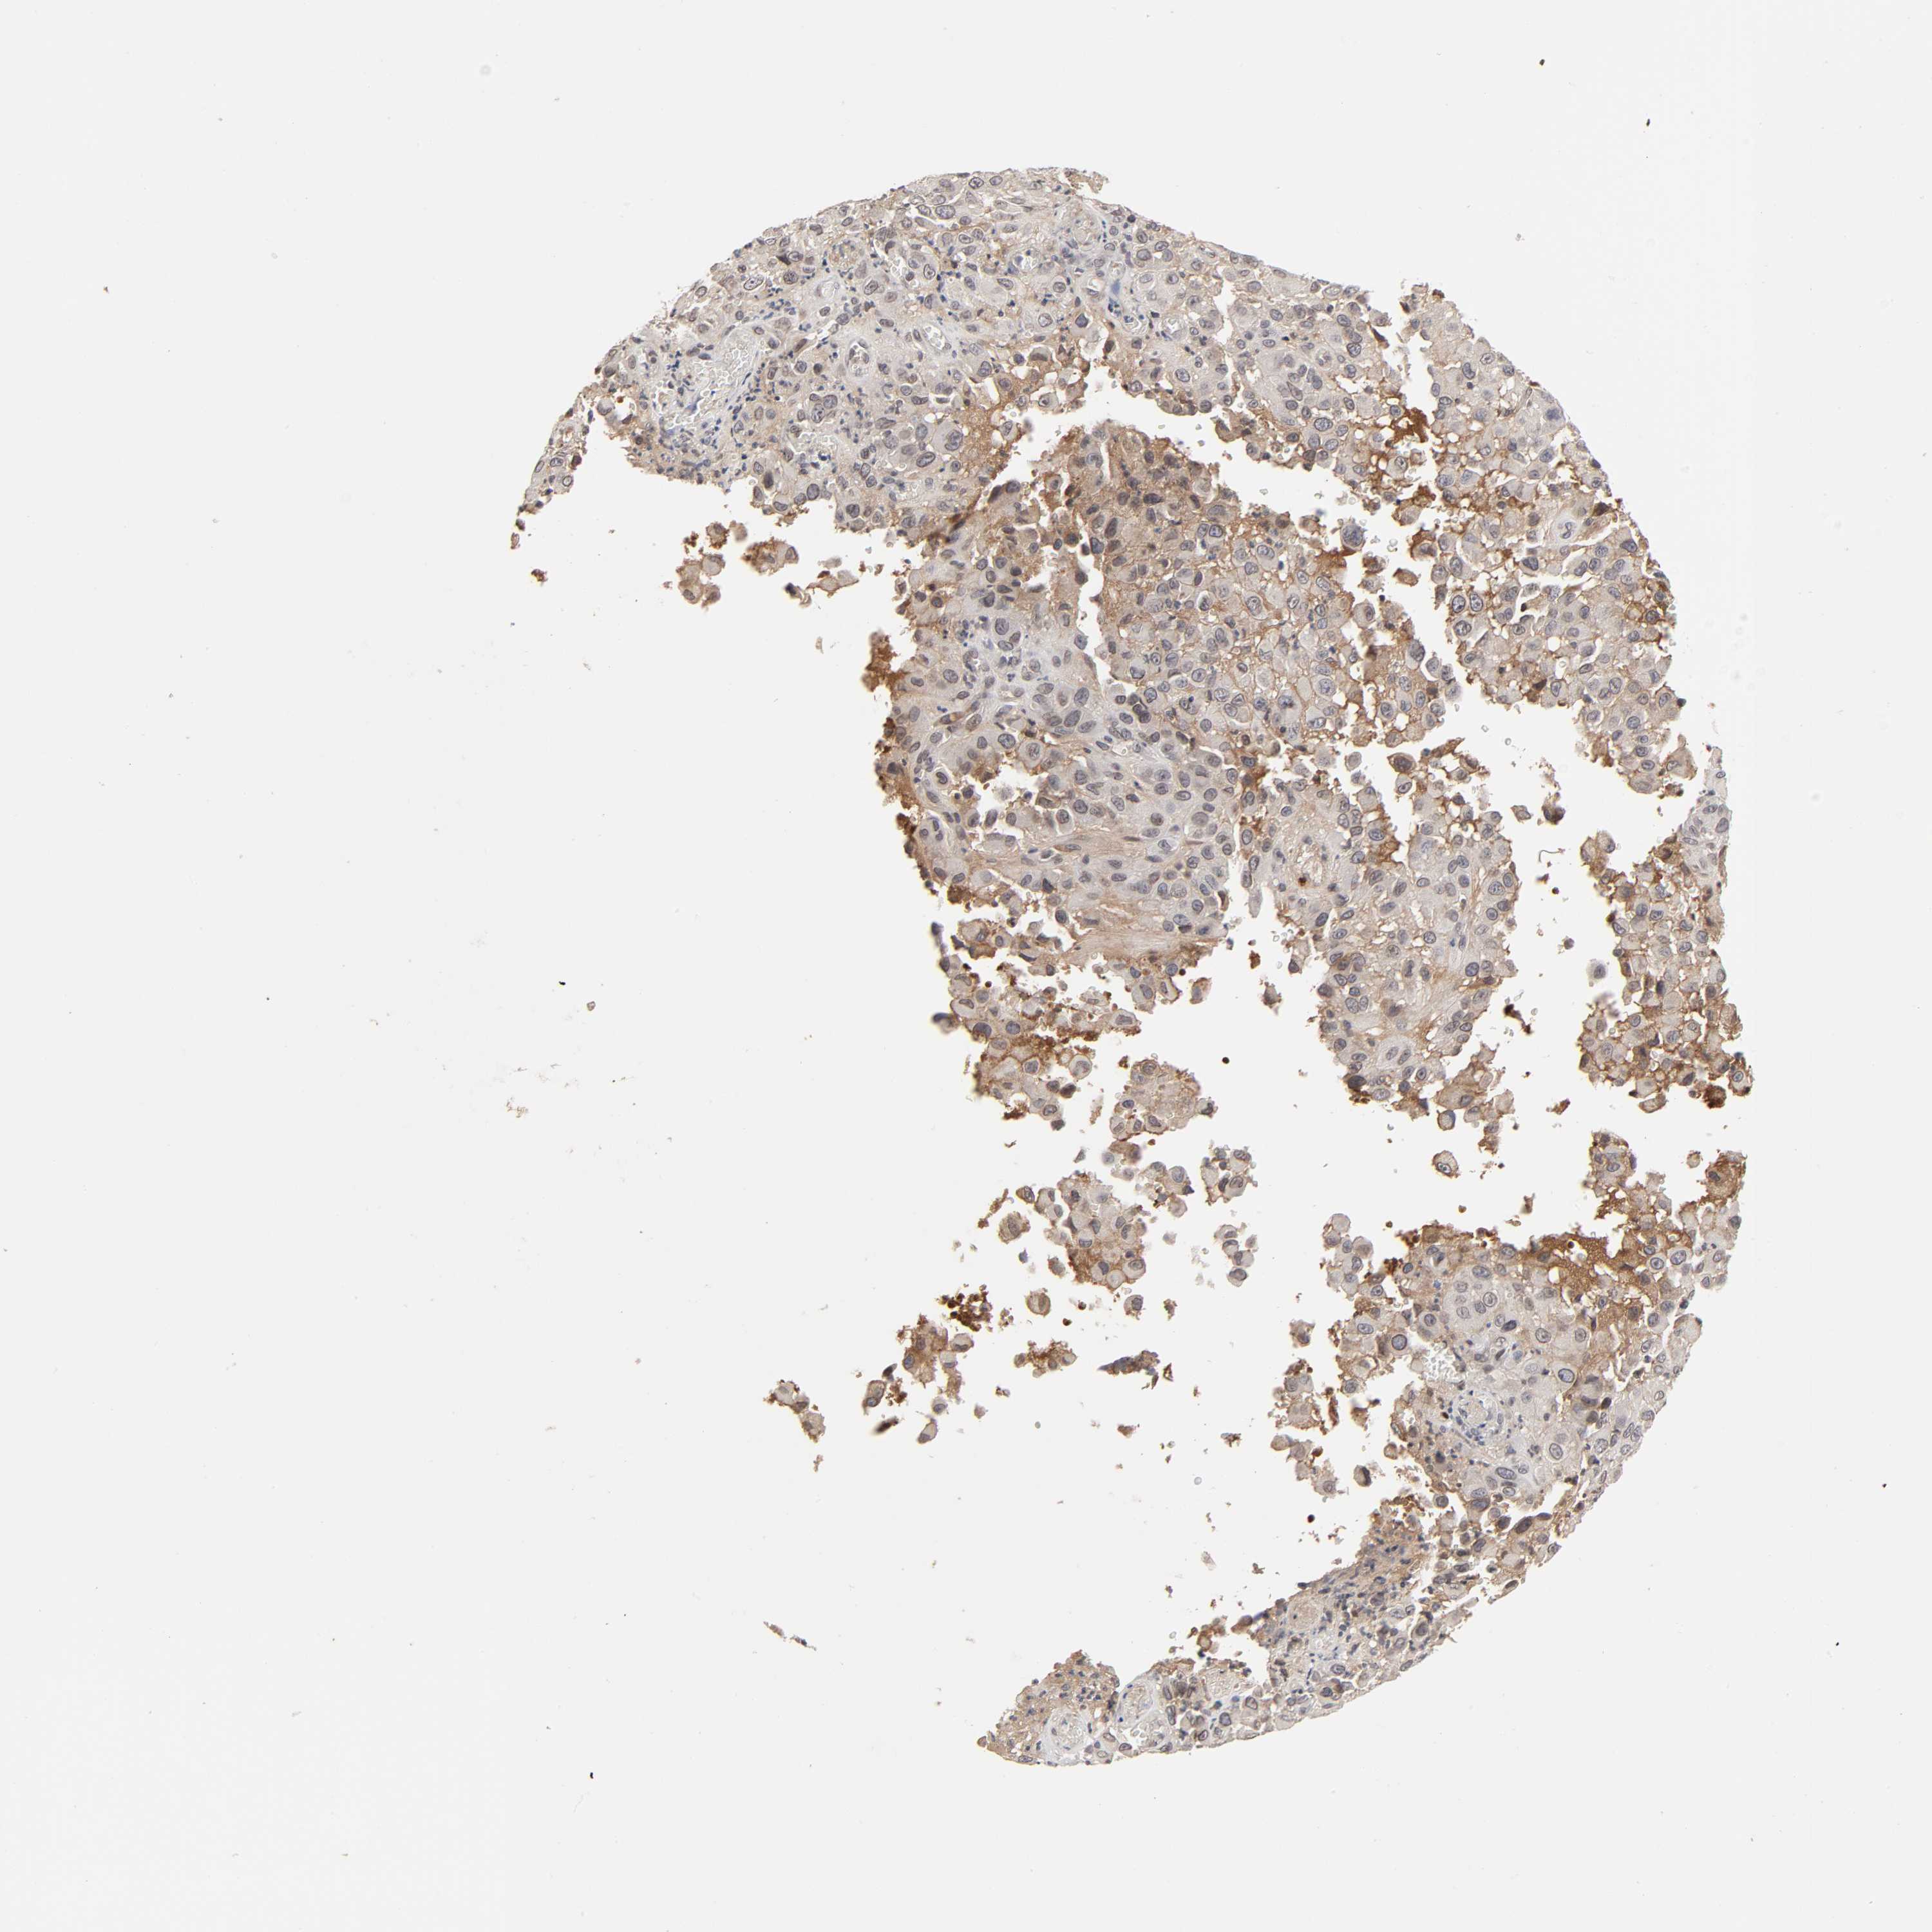

MELANOMA - Protein expressioni

A mouse-over function shows sample information and annotation data. Click on an image to view it in a full screen mode. Samples can be filtered based on level of antibody staining by selecting one or several of the following categories: high, medium, low and not detected. The assay and annotation is described here.

Note that samples used for immunohistochemistry by the Human Protein Atlas do not correspond to samples in the TCGA dataset.

Antibody stainingi

Antibody staining in the annotated cell types in the current human tissue is reported as not detected, low, medium, or high, based on conventional immunohistochemistry profiling in selected tissues. This score is based on the combination of the staining intensity and fraction of stained cells.

Each image is clickable and will lead to virtual microscopy that enables deeper exploration of all samples and also displays staining intensity scores, fraction scores and subcellular localization as well as patient and tissue information for each sample.

Antibody HPA004732

Staining

High

Medium

Low

Not detected

Intensity

Strong

Moderate

Weak

Negative

Quantity

>75%

75%-25%

<25%

None

Location

Nuclear

Cytoplasmic/membranous

Cytoplasmic/membranous,nuclear

Malignant melanoma, NOS

Malignant melanoma, Metastatic site